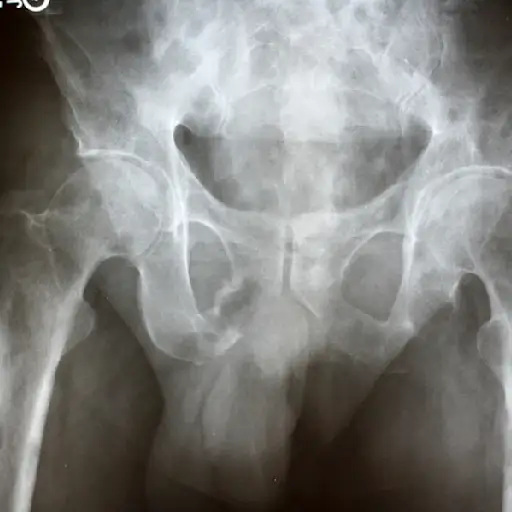

骨骼中转移的风险

超过一半的阶段4乳腺癌患者体验骨转移据Murercancer.org称。通常是第一个地方乳腺癌蔓延,骨骼最常见的影响包括肋骨,脊柱,骨盆和臂和腿部。如果您怀疑癌症已经扩散到骨骼,重要的是要快速检查,因为您可能能够防止伴侣迅速治疗。

骨骼中转移的迹象

注意突然出现的新疼痛,特别是那些不能通过休息或躺下而消失的疼痛。其他症状包括:

- 无法移动(可能表明骨折)

- 任何部位麻木或无力

- 便秘

减少警觉性,疲劳,弱点,恶心,食欲丧失,脱水可以是钙,因为骨分解而在血液中升起。